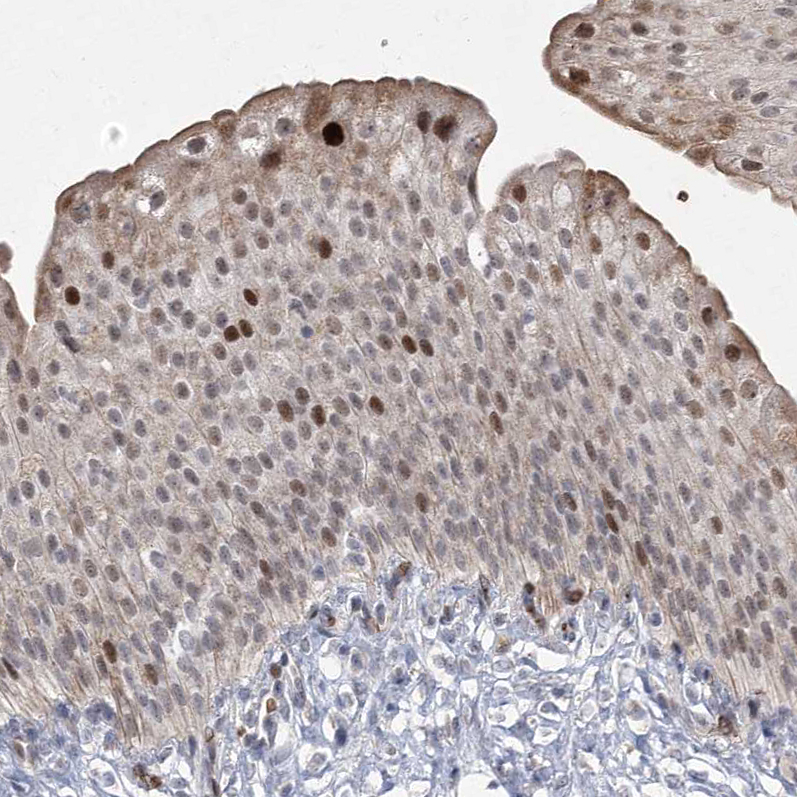

Immunohistochemical staining of human urinary bladder shows strong nuclear positivity in urothelial cells.